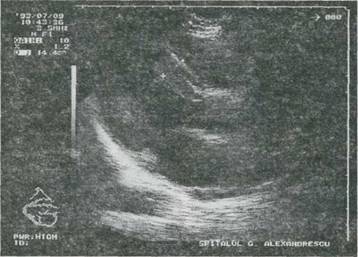

Fig. 9-24. Fibroelastoza endocardica la un sugar în vârsta de 3 luni. Echocardiografie 2-D, sectiune apicata 4 camere si mod M. Dilatare importanta ventriculara stânga, aspect îngrosat cu echodensitate mult crescuta (hiperecogenitate intensa) a endocardului aparatului valvei mitrale; amplitudine redusa de miscare a valvei mitrale.